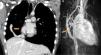

Case reportsCase 1 (partial anomalous venous return with infracardiac drainage)We describe the case of a 14-year-old girl assessed for an incidental finding on chest X-ray (pulmonary asymmetry). The chest X-ray revealed right pulmonary hypoplasia as well as an anomalous pulmonary vein descending below the diaphragm creating a curved shape on the right side, the scimitar sign. Echocardiography showed dextrocardia with apex on the left, at least two pulmonary veins draining into the left atrium, intact atrial and ventricular septa, no dilation of the cardiac chambers, preserved global biventricular systolic function and no signs of pulmonary hypertension. Computed tomography (CT) confirmed and better characterized these imaging findings (Figure 1A). Magnetic resonance imaging (MRI) (Figure 1B), in addition to angiographic evaluation, was also important for excluding associated congenital heart disease, and for assessment of right ventricular (RV) systolic function and volume, as well as left-to-right shunting (Qp:Qs 1:2). Given that the patient was asymptomatic and there was no evidence of cardiac functional impairment, a conservative strategy was adopted.

(A) Coronal-reformatted contrast-enhanced computed tomography showing the scimitar vein draining into the inferior vena cava (arrow) as well as right pulmonary hypoplasia with left lung expansion; (B) sagittal four-dimensional magnetic resonance imaging angiographic image also demonstrating the scimitar vein (orange arrow).